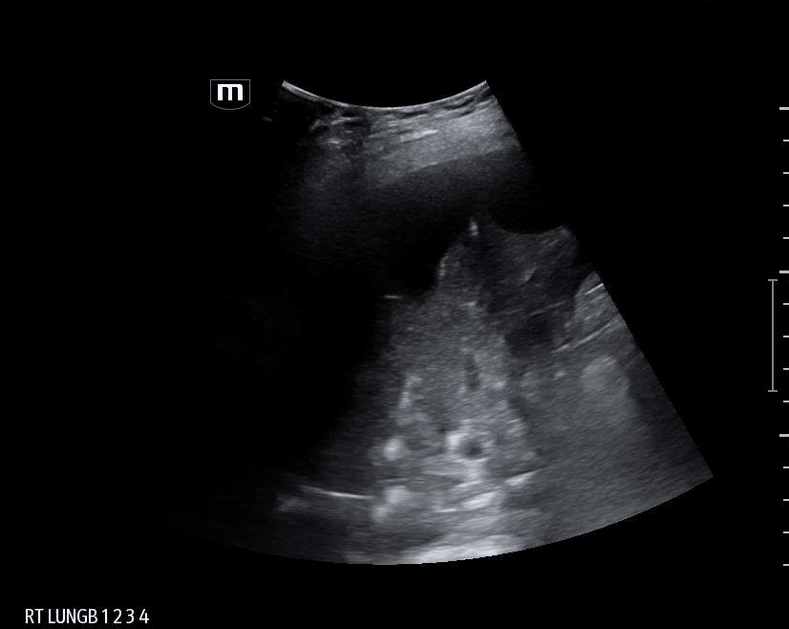

What do we see in this pt’s US?!

Right lung base

Patient’s CT chest came back positive for right sided aspiration pneumonia and right lung collapse secondary to pleural effusions.